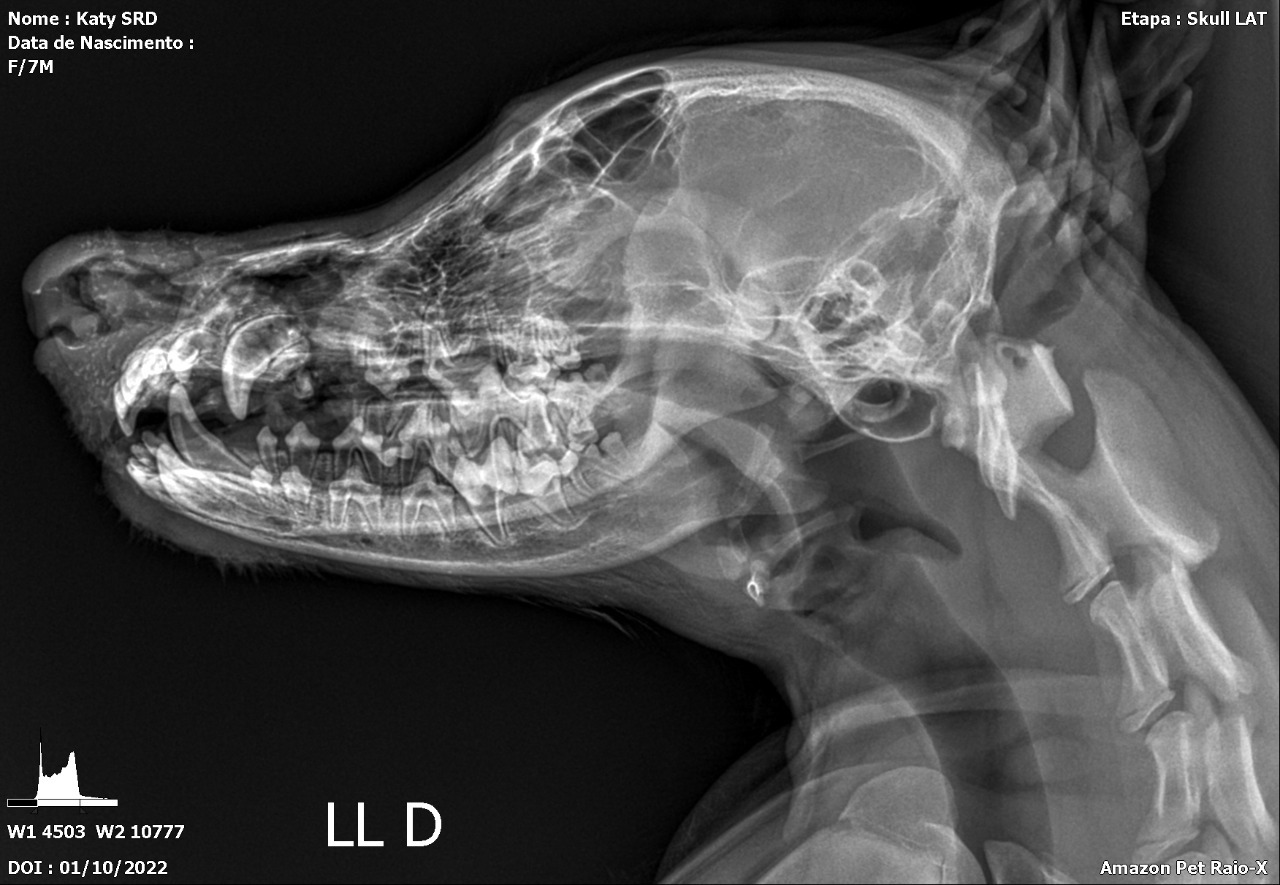

A maxilectomia é um procedimento cirúrgico em que parte ou toda a maxila é removida ou parcialmente removida. Esta cirurgia de maxilectomia é frequentemente realizada para ressecção de neoplasia oral ou traumas. Neste contexto o objetivo deste trabalho é relatar o procedimento cirúrgico de maxlectomia rosto central bilateral em um cão doméstico atendido em uma clínica veterinária na Região Metropolitana de Manaus, Estado do Amazonas. Para isso, o procedimento de maxilectomia foi desenvolvido através de técnicas que envolvem excisão parcial ou total dos ossos incisivos, nasal, maxilar, palatino, vômer, lacrimal e zigomático, dentes e tecidos moles. Para esse procedimento, foi realizado a anestesia geral inalatória. Após quinze dias da cirurgia foi realizado a remoção dos pontos visualizando uma cicatrização adequada do local da incisão. Os animais que realizam esta cirurgia têm prognóstico positivo, no entanto só podem consumir alimentos pastosos.